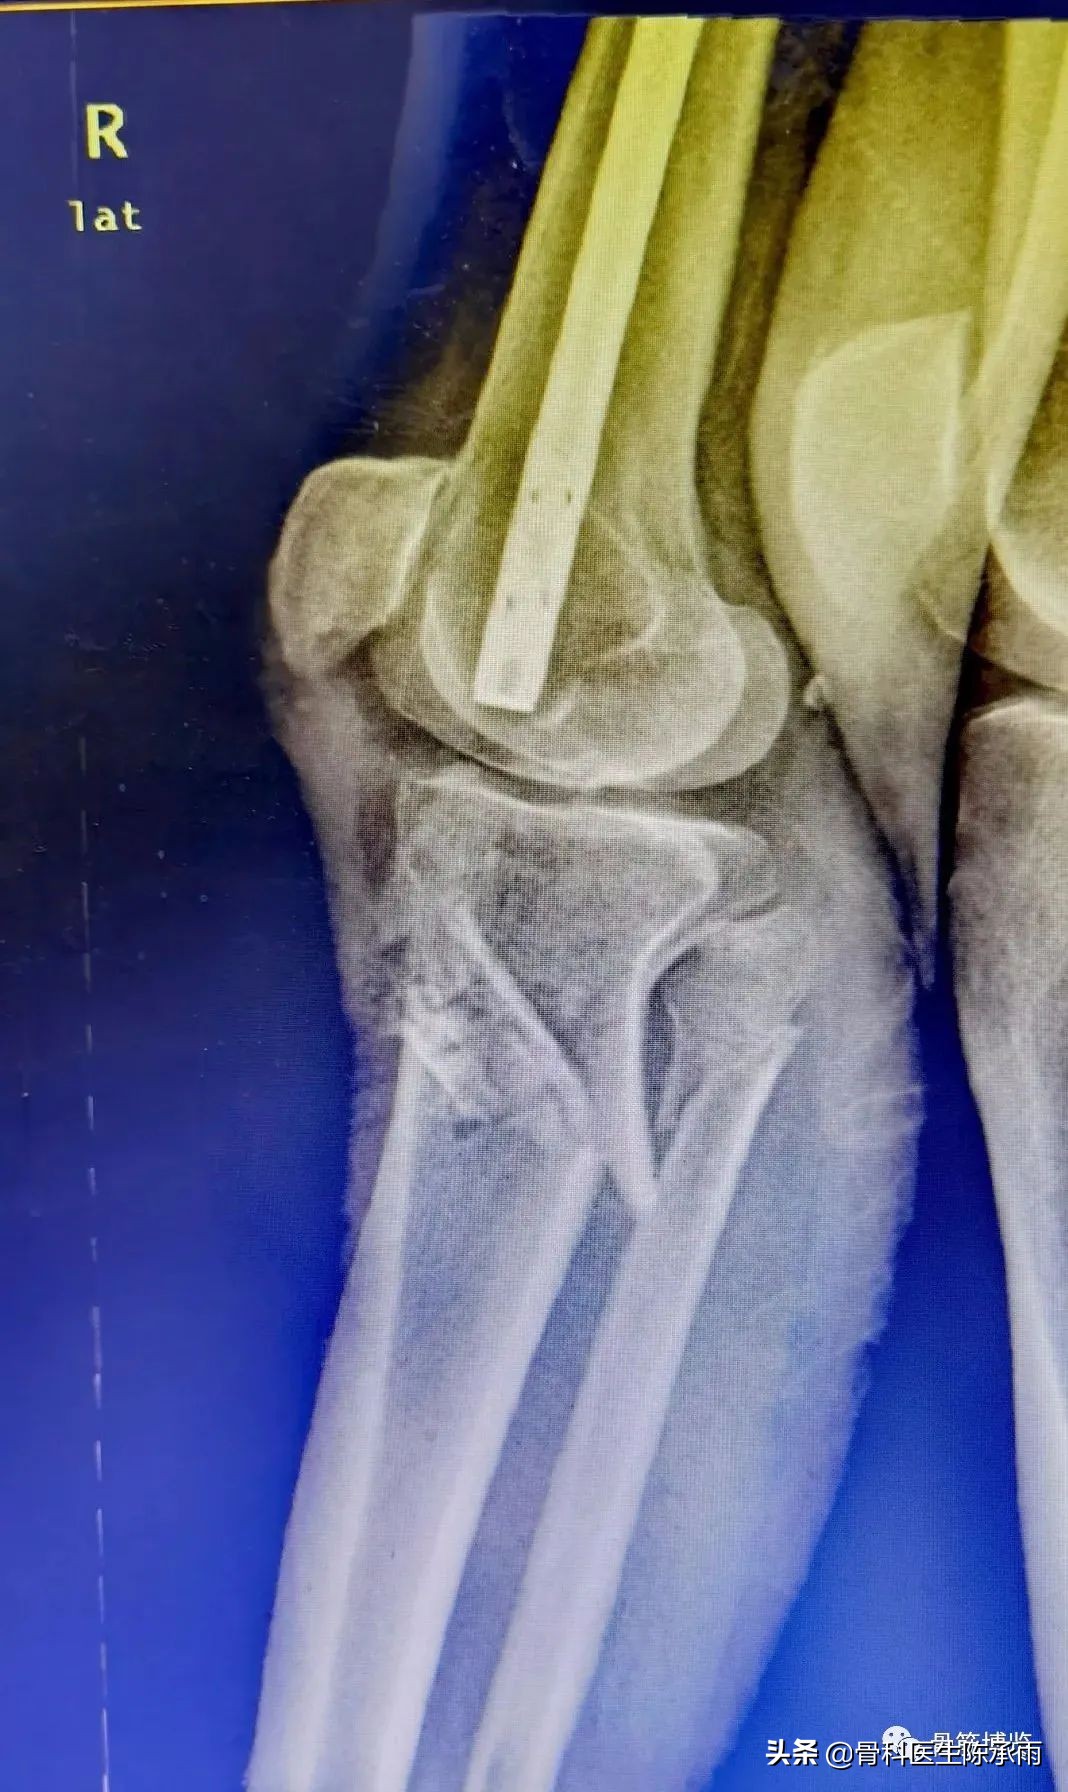

这2例患者皮肤条件差,全身多发骨折,小腿皮肤条件差,1例筋膜高压切开,1例整个小腿布满张力性水泡,胫骨骨折都在伤后30天才能手术。

下例胫平台骨折皮肤条件差,内侧板取两端小切口置入内板固定。胫骨结节处撕脱骨折以1枚拉力螺钉固定。